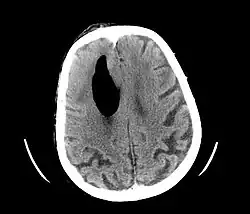

In der Computertomographie (CT) grenzen sich die Gasblasen deutlich gegen das Gewebe ab, zum Teil können sie schon in einer normalen Röntgenaufnahme erkennbar sein. Bei der im CT gängigen Rückenlage steigen die Gasblasen üblicherweise auf und sammeln sich vor den Frontallappen, dies wird im englischen Sprachraum als „Mount Fuji sign“ bezeichnet.